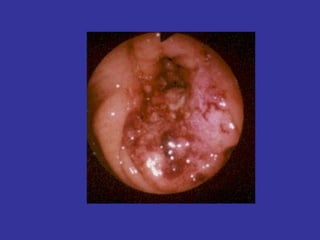

PÓLIPOS

CANCER DE COLON

PÓLIPOS RECTALES

CANCER DE RECTO